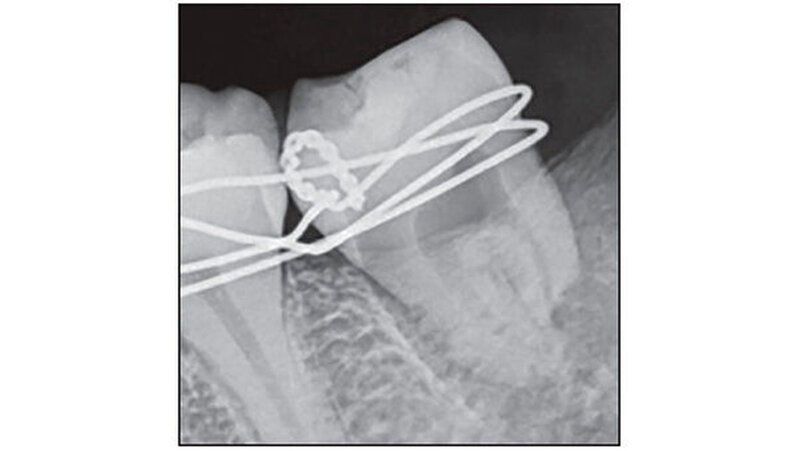

Bei einer Röntgenkontrolle nach vier Wochen präsentierte sich ein zufriedenstellender Heilungsverlauf am periapikalen Bereich. Der transplantierte Zahn wurde als stabil befunden. Der Wurzelkanal des Zahns 38 wurde mit Gutta Percha (Dentsply Maillefer, Ballaigues, Schweiz) gefüllt, danach folgte eine Versiegelung mit Sealapex (Kerr Corporation CA, USA). Die Wurzelkanalfüllung wurde per Röntgenbild überprüft (Abbildung 4). Die Patientin spülte anschließend drei- bis viermal täglich einen Monat lang mit warmer Kochsalzlösung.

Nach sechs, neun, 12 und 18 Monaten folgten weitere klinische und radiologische Kontrollen (Abbildungen 4 und 5). Bei jedem Besuch wurden der Mundhygienestatus, die Stabilität des Transplantats, die Sulkustiefe, Okklusion und die Wurzelresorption überprüft. Die vollständige Heilung war nach 18 Monaten erreicht.